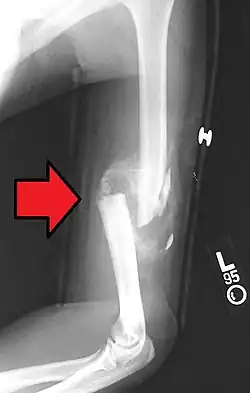

Midshaft humerus fracture with callus formation

The cause of a humerus fracture is usually physical trauma such as a fall.[1] Other causes include conditions such as cancer in the bone.[2] Types include proximal humeral fractures, humeral shaft fractures, and distal humeral fractures.[1][2] Diagnosis is generally confirmed by X-rays.[2] A CT scan may be done in proximal fractures to gather further details.[2]

Definitive diagnosis of humerus fractures is typically made through radiographic imaging. For proximal fractures, X-rays can be taken from a scapular anteroposterior (AP) view, which takes an image of the front of the shoulder region from an angle, a scapular Y view, which takes an image of the back of the shoulder region from an angle, and an axillar lateral view, which has the patient lie on his or her back, lift the bottom half of the arm up to the side, and have an image taken of the axilla region underneath the shoulder.[9] Fractures of the humerus shaft are usually correctly identified with radiographic images taken from the AP and lateral viewpoints.[12] Damage to the radial nerve from a shaft fracture can be identified by an inability to bend the hand backwards or by decreased sensation in the back of the hand.[5] Images of the distal region are often of poor quality due to the patient being unable to extend the elbow because of pain. If a severe distal fracture is suspected, then a computed tomography (CT) scan can provide greater detail of the fracture. Nondisplaced distal fractures may not be directly visible; they may only be visible due to fat being displaced because of internal bleeding in the elbow.[7]